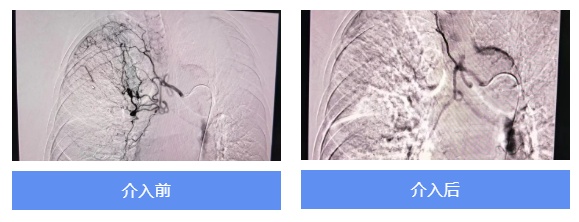

当晚20点30分,患者进入DSA室,正式开始医院第一例支气管动脉栓塞术。手术过程顺利,咯血原因被很快找到,罪魁祸首是右肺上叶肺动脉分支处的一个动静脉瘘(支气管动脉-肺动脉分支瘘)。由于动静脉瘘再次发生大咯血的概率极大,甚至会威胁生命,所以此次介入手术可谓“一场及时雨”。

21点30分,患者安返病房,心电监护提示生命体征平稳,且无胸闷不适和肢体活动障碍,这也预示着术前担心的脊髓动脉栓塞导致的截瘫被成功规避。

次日清晨6点45分,医生查房查看该患者伤口处无异常,肺部听诊较前啰音明显减少,且无胸闷咳嗽,未再咯血。患者家属感激道:“宝山医院的医生这次真的救了我们一命!”